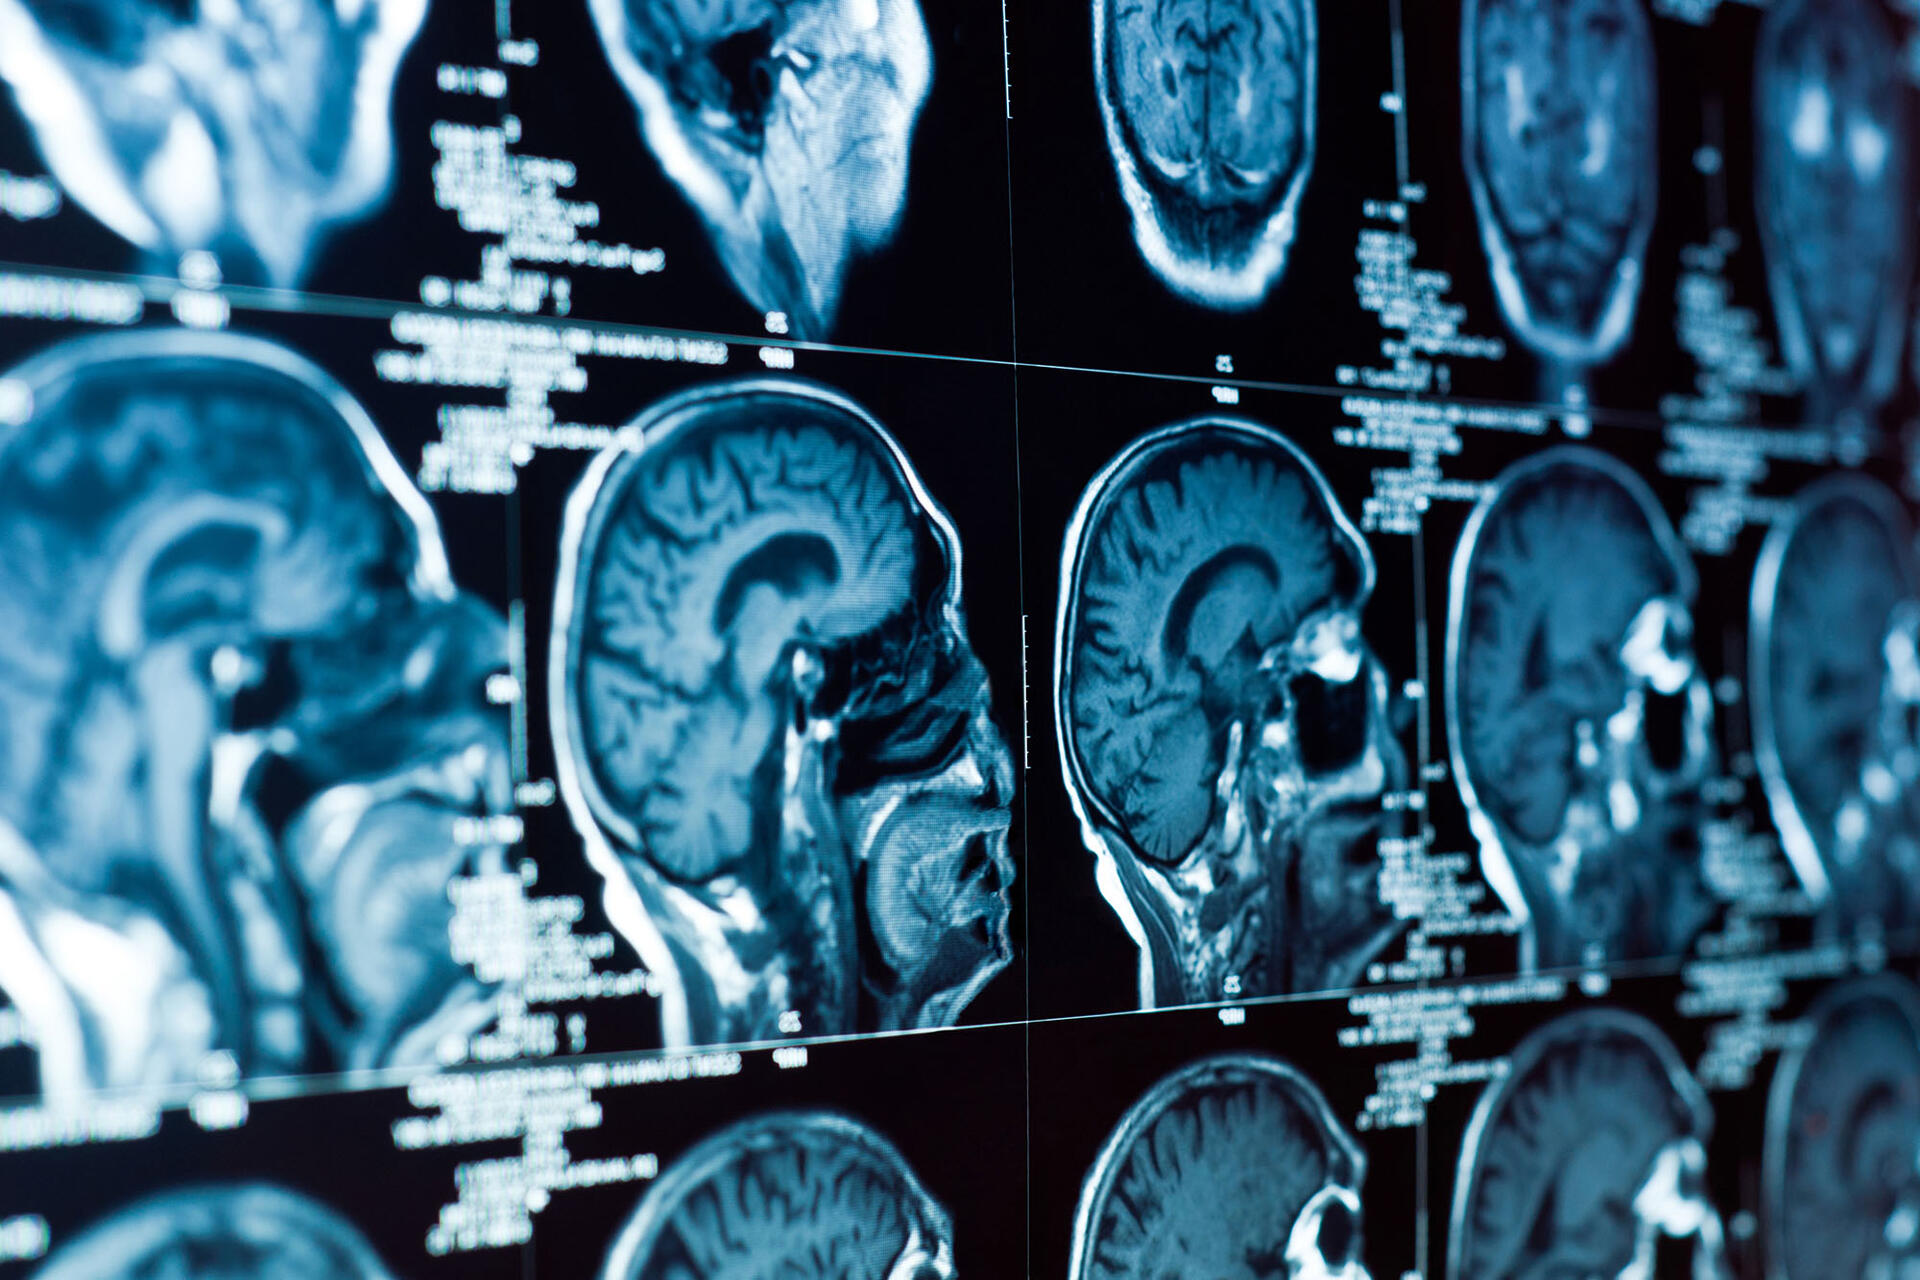

What do these baffling statistics about seemingly disparate diseases have in common? Ortiz’s research holds the answer: “Individuals with Type II diabetes are up to four times more likely to develop Alzheimer’s disease,” he said.

Ortiz researches the connections between these two diseases. Ortiz emphasizes how important this work is, especially given the United States’ rapidly aging population. He states, “It is crucial to investigate and understand the mechanisms between these two devastating modalities for early preventative measures and development of therapeutics.”

Looking toward the future, Ortiz sees himself continuing with his research with the hopes that it can help lower the number of Americans with Alzheimer’s. Ortiz says, “My end academic career goal is to strive to secure a faculty position at an institution, where I will continue to focus on the detrimental effects of impaired energy metabolism in relation to the brain.”